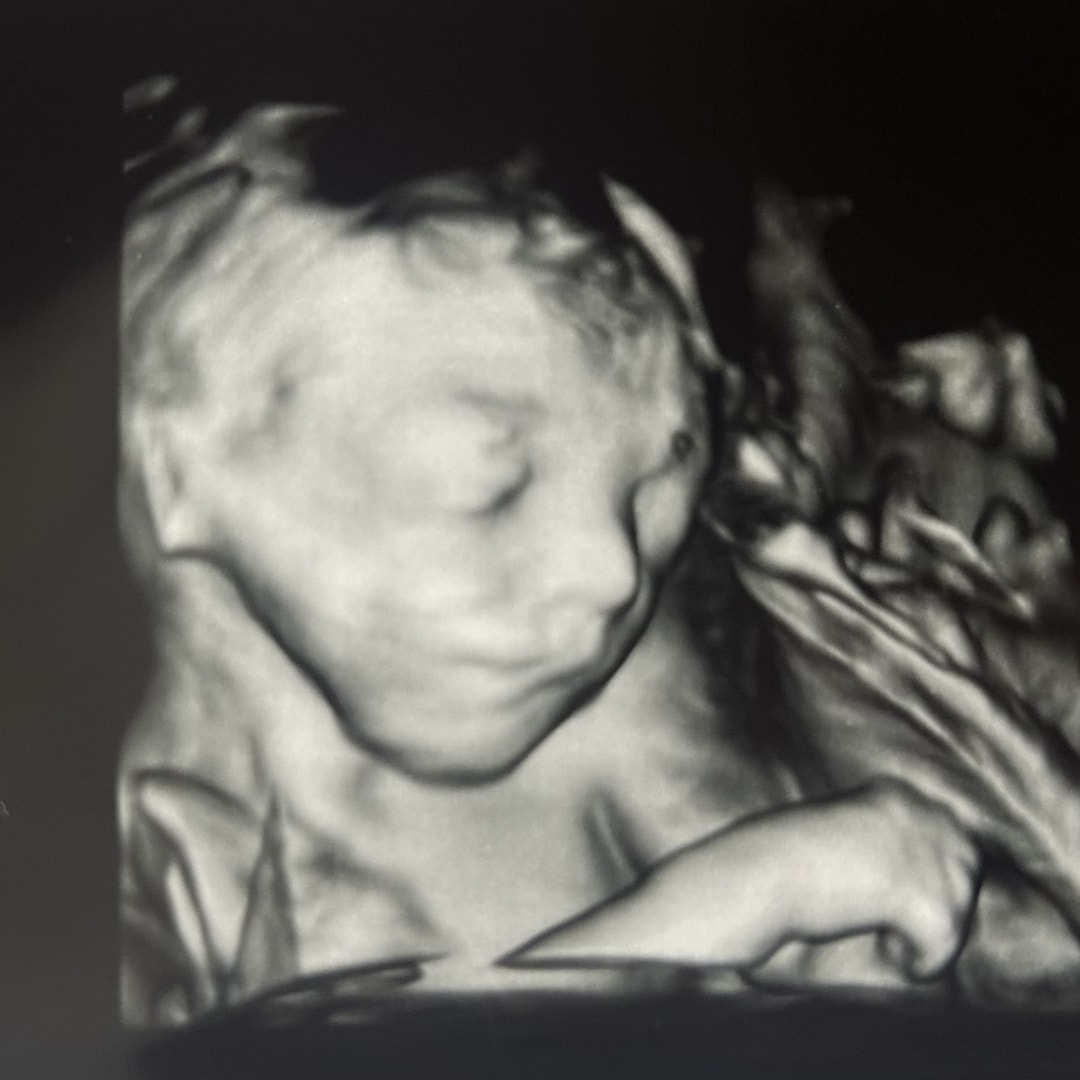

Violet Grace

Violet Grace🥰